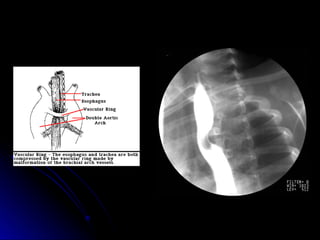

Vascular Rings

 Uncommon

Uncommon

 Signs include stridor, vomiting and difficulty

Signs include stridor, vomiting and difficulty

swallowing.

 Barium swallow can be diagnostic, but may

Barium swallow can be diagnostic, but may

need chest MRI.

 Sometimes may need cardiac

Sometimes may need cardiac

catheterization